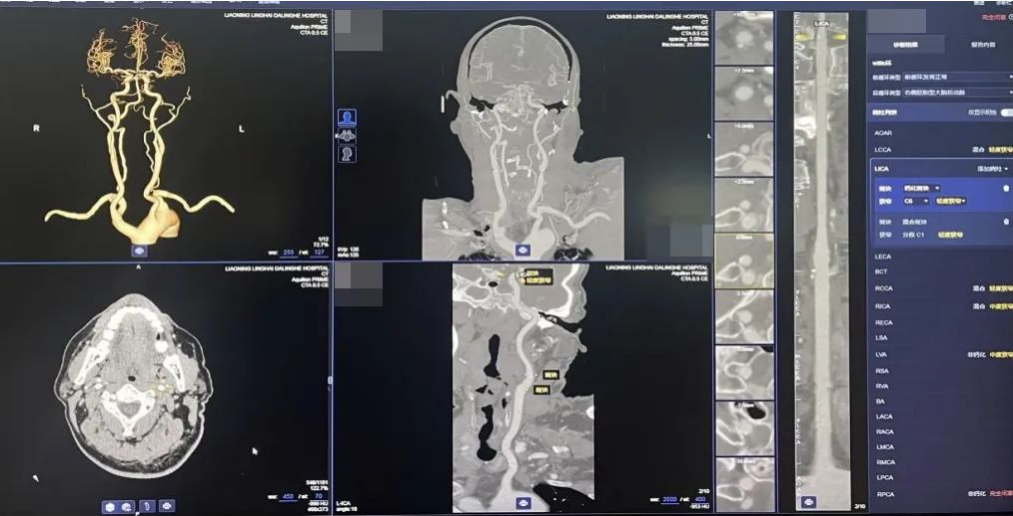

AI冠脉、头颈部CTA血管斑块辅助检测

能自动识别血管,完成血管分段的标识,同时能自动完成血管狭窄和斑块性质评估,为斑块风险提供建议,提高诊断效率,促进冠心病、诊治标准化,帮助医生快速明确病变位置和范围。同时,基于重组的图像可以对常见血管病变进行智能诊断,包括血管狭窄及斑块分析、颅内动脉瘤等,实现CTA检查全流程覆盖。